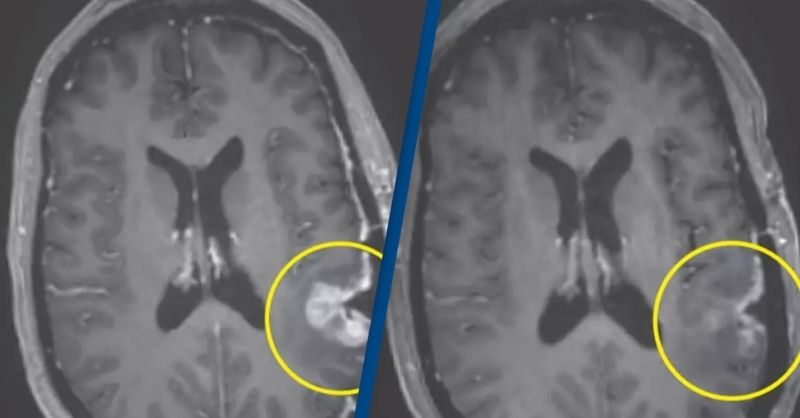

Doctor remains cancer-free one year after using world-first treatment he developed for terminal brain tumor

A doctor has provided an update one year after becoming the first person to receive a groundbreaking treatment for his terminal brain cancer. Richard Scolyer, a globally recognized...